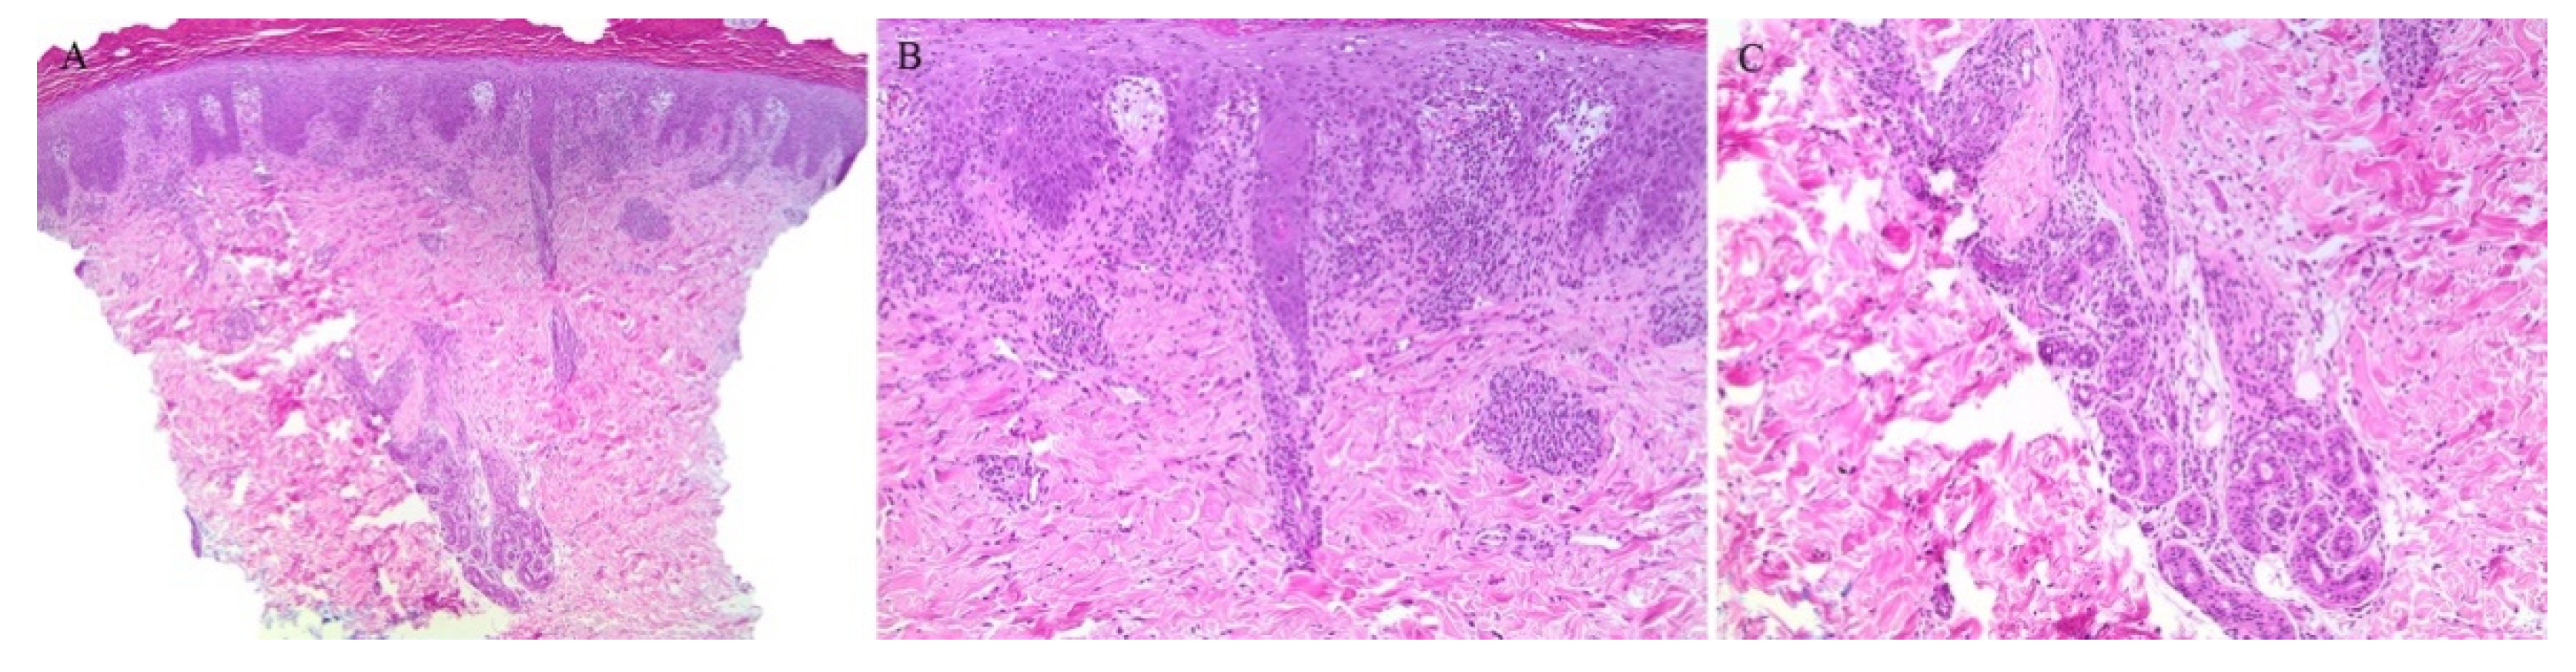

Lichen planus is the prototype lichenoid dermatitis characterized by a self-limiting eruption of pruritic flat-topped violaceous papules. On histopathology, hyperkeratosis, hypergranulosis, irregular acanthosis, and subepidermal clefts known as Max Joseph spaces are observed. A band-like lymphohistiocytic infiltrate is also seen. Distinct adnexotropic variants of lichen planus have been described (Figure 1). These include follicular lichen planus, lichen planus follicularis tumidus, and syringotropic lichen planus.

Figure 1.

(A–C) Lichen planus with follicular involvement.

Lichen planopilaris, or follicular lichen planus, is a distinct variant of lichen planus whereby inflammation is seen around the hair follicle both clinically and histologically (Figure 1). Clinically, this presents with perifollicular erythema, follicular keratotic plugs, and a scarring alopecia [1,2].

Lichen planus follicularis tumidus (LPFT) is another distinct adnexotropic variant of lichen planus. Clinically, it is characterized by the presence of typical lichen planus lesions with the addition of comedo-like lesions and keratin-filled cysts, most commonly located in the retroauricular area. Most patients have classical lichen planus lesions on other parts of the body. On histopathology, the typical features of lichen planus are seen along with the involvement of the hair follicle. Follicular hyperkeratosis is observed and the follicular infundibulum is cystic and dilated. The follicular infundibulum is also surrounded by a lichenoid infiltrate [3]. Recognizing this entity is important as the differential diagnosis includes cutaneous lupus erythematosus (LE) with cysts and comedones and follicular mycosis fungoides (MF). Cutaneous LE is characterized by increased mucin deposition not seen in LPFT, while the presence of epidermotropism and an infiltrate of atypical lymphocytes is noted in follicular MF and not in LPFT [4].